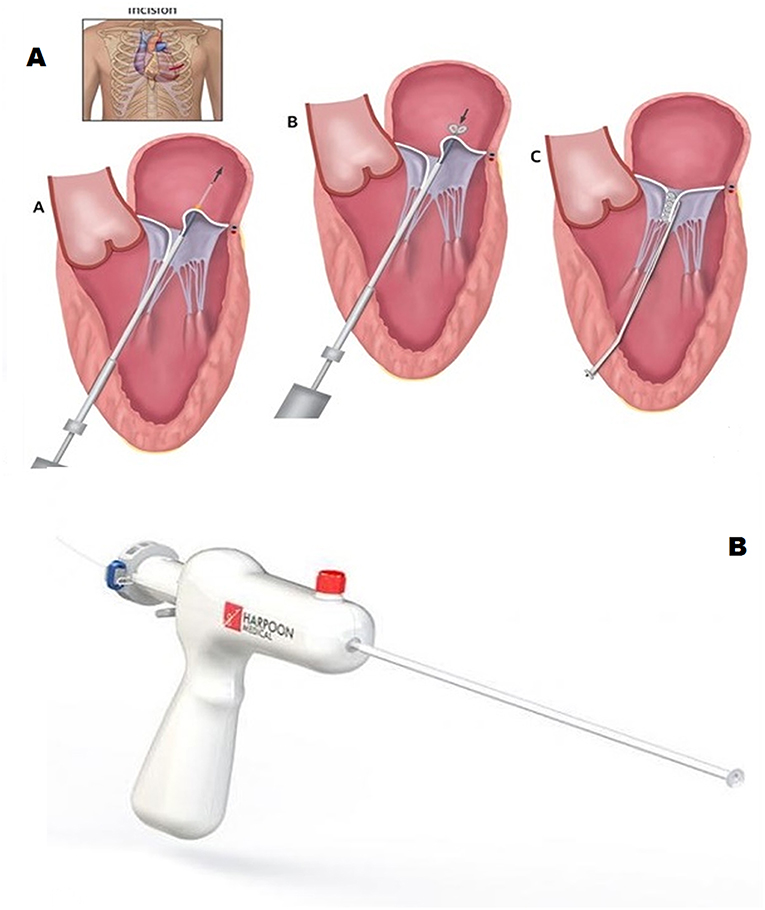

Frontiers | Transcatheter Mitral Valve Chordal Repair: Current

www.frontiersin.org

www.frontiersin.org

mitral transcatheter chordae chordal frontiersin indications perspectives harpoon implantation surgical fcvm

Characteristics Of The Transcatheter Mitral Valve Chord Repair Devices

www.researchgate.net

www.researchgate.net

harpoon mitral chord transcatheter valve tsd edwards devices

Frontiers | Transcatheter Mitral Valve Chordal Repair: Current

www.frontiersin.org

www.frontiersin.org

chordal mitral frontiersin perspectives transcatheter indications repair future fcvm

Transcatheter Mitral Valve Chordal Repair: Current Indications And

europepmc.org

europepmc.org